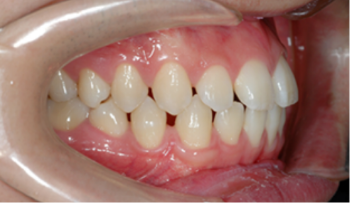

치아 교정은 바로 '교합'을 바로잡는 과정입니다.

단순히 삐뚤어진 치아를 가지런히 하거나 튀어나온 입을 넣는 것이 아니라,

위아래 턱뼈의 관계를 정상화하고 바르게 씹고 발음할 수 있도록 도와줍니다.

그 결과, 기능을 회복하고 아름다운 얼굴 모양을 완성할 수 있습니다.

결국, 교정 치료란 치아 기능을 회복해 균형 잡힌 아름다움을 만드는 일입니다.